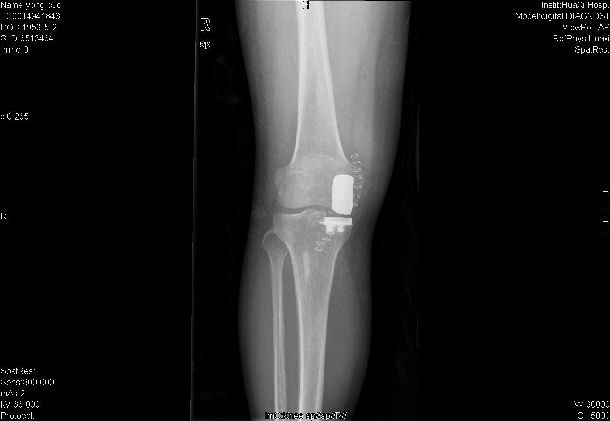

膝關(guān)節(jié)單髁置換術(shù)

膝關(guān)節(jié)單髁置換術(shù)針對(duì)的是膝關(guān)節(jié)單間室骨關(guān)節(jié)炎<病患,通過微創(chuàng)手術(shù)僅對(duì)膝關(guān)節(jié)病變的一側(cè)間室表面進(jìn)行置換,更換病變的軟骨面,保留全部的韌帶組織和其余間室關(guān)節(jié)軟骨,從而實(shí)現(xiàn)術(shù)后的快速康復(fù)。

單髁置換術(shù)適應(yīng)癥:(1)局限于膝關(guān)節(jié)單側(cè)間室的骨性關(guān)節(jié)炎,疼痛嚴(yán)重,需要接受關(guān)節(jié)置換手術(shù)治療;(2)X線征象要求患側(cè)間室關(guān)節(jié)間隙嚴(yán)重變窄,而對(duì)側(cè)間室和髕股關(guān)節(jié)間室保留全層軟骨者;(2)膝關(guān)節(jié)畸形:內(nèi)外翻小于15°,屈曲攣縮不超過15°;(3)術(shù)前膝關(guān)節(jié)屈曲至少 100°的患者;(4)、膝關(guān)節(jié)周圍韌帶結(jié)構(gòu)功能完整的患者。